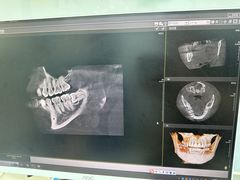

• 牙博士口腔品牌连锁(杨浦店)

• -牙博士口腔品牌连锁(杨浦店)